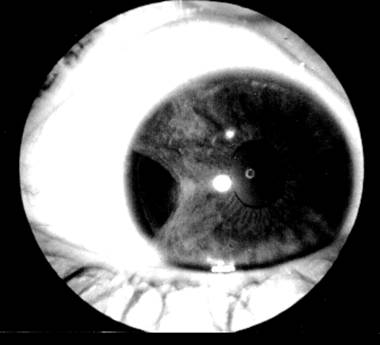

Contuzie oculara cu hipema

PLANSA VI - TRAUMATISME OCULARE

Sunt dominate de prezenta hipemei (sange in camera anterioara-vezi plansa), care se depune decliv, de obicei in unghiul camerular inferior, in functie de pozitia pacientului. Umorul apos are tenta hematica. Hipema se asociaza de regula de cresterea tensiunii intraoculare, datorita blocarii emonctoriilor oculare cu celule hematice. Complicatia cea mai grava, ramane insa impregnatia hematica a corneei, cu pierderea ireversibila a transparentei corneene.